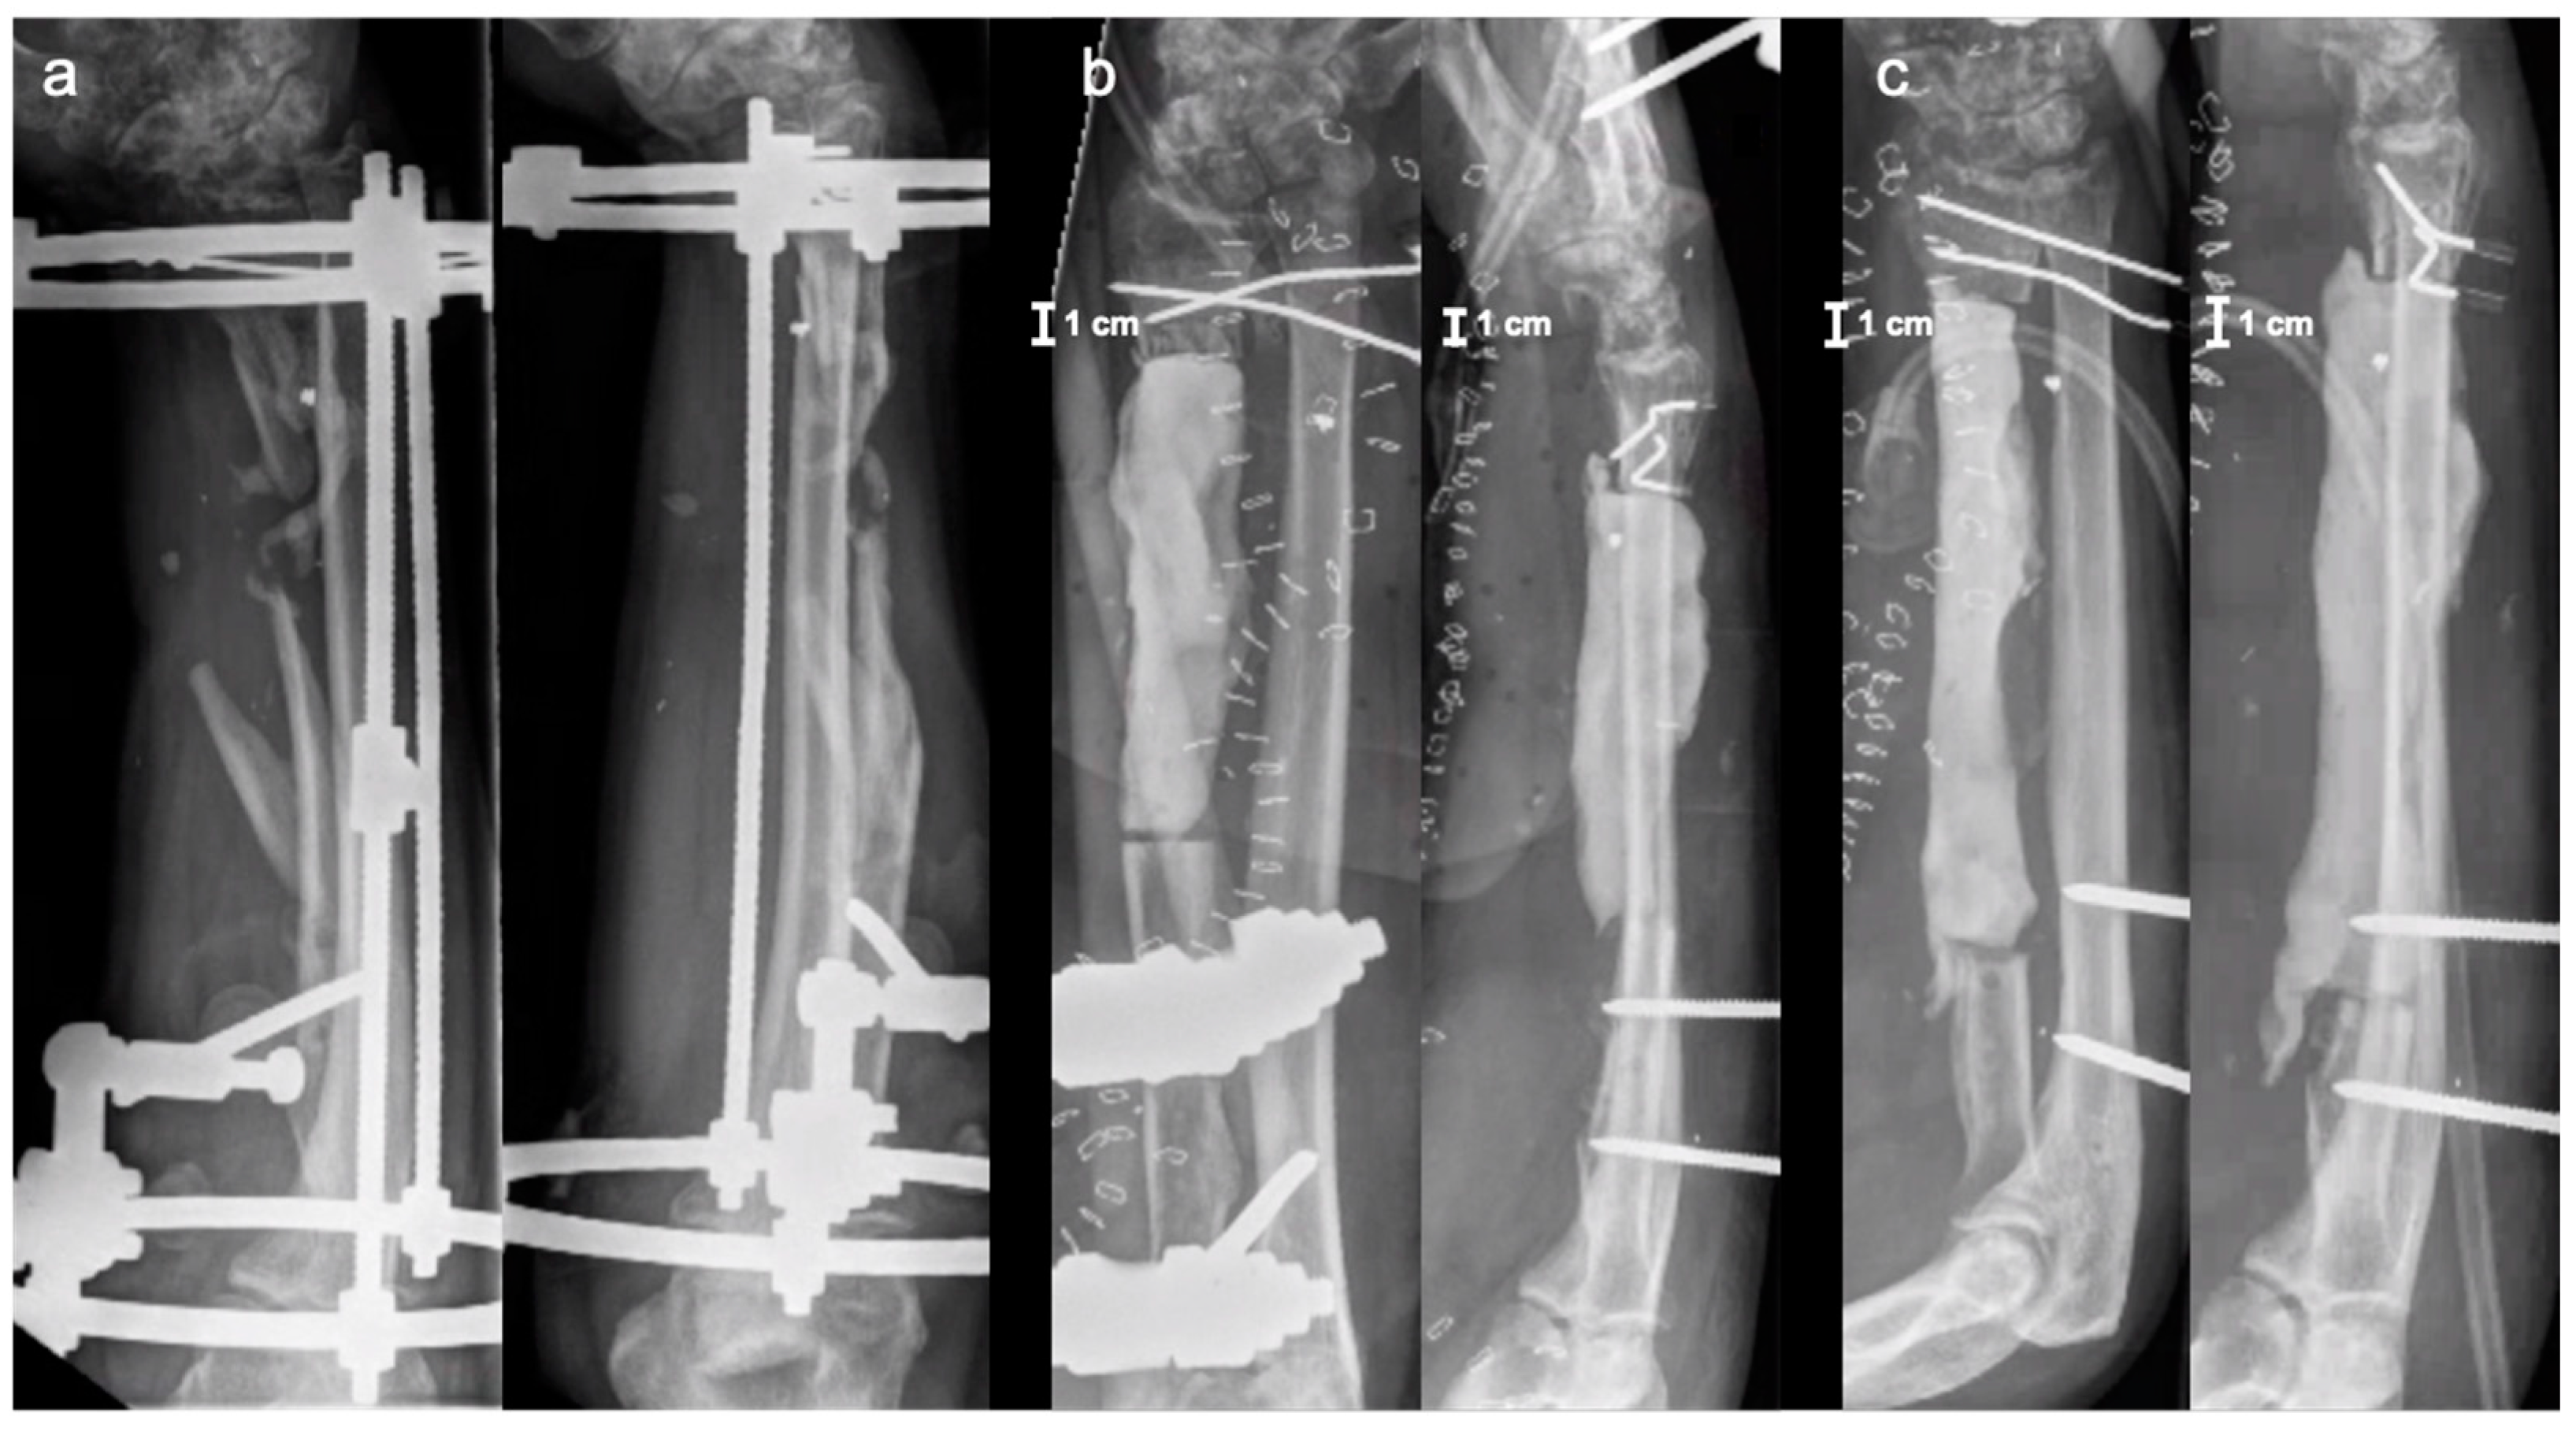

2. Case Report